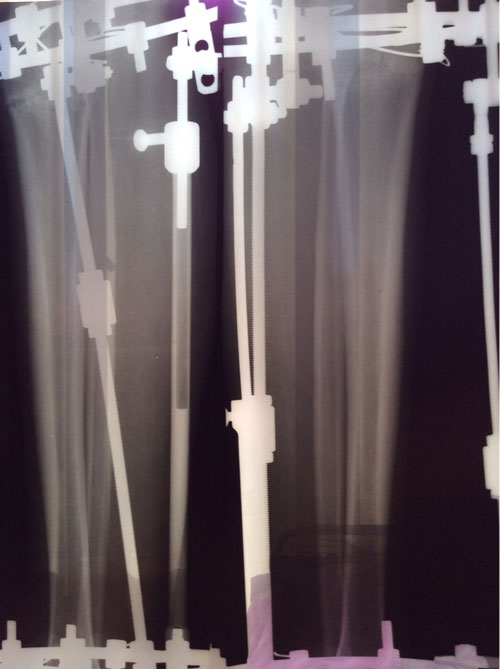

Nikol, ножки супер!

Дата операции 04.02.2014г.

Дата снятия аппаратов 05.05.2014г.

Срок лечения 89 дней.